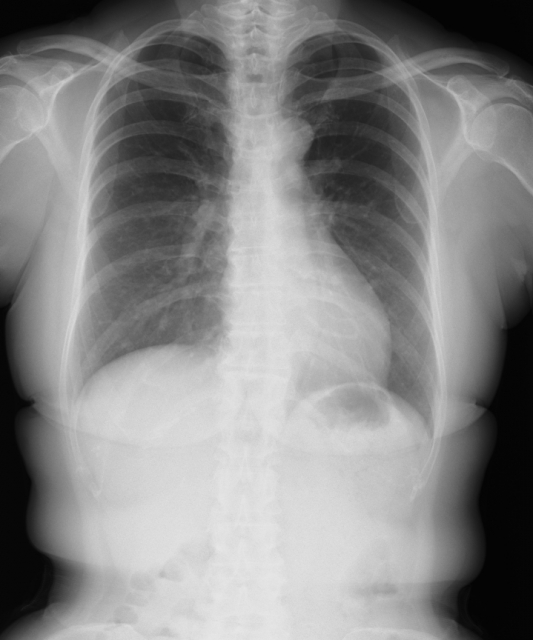

その他の影響する病気がないかどうか、心臓の構造的な異常がないかどうかを確認するために、心電図だけでなく、採血、胸部レントゲン、超音波検査などを行います。